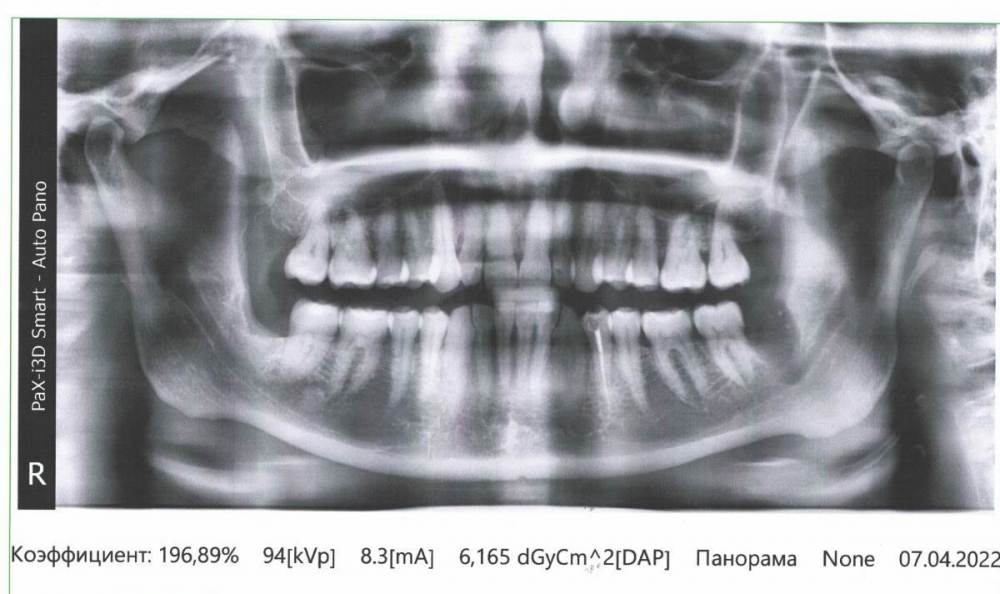

СмирноваД Опубликовано 29 июня, 2023 Поделиться Опубликовано 29 июня, 2023 Уважаемые стоматологи. Прошу Вашей помощи в поиске проблемы. Зуб удалили 2 года назад, но покоя там слизистая не дает. Болит, Разговаривать не дает вообще. Как буд-то там все пришили, и щеку и тяж со стороны горла. Какая-то шишка растет в конце верхней челюсти и как-будто давит там. Срослось оно вот таким образом "V"(со слов врача). Дергает щеку сильно , как-будто она прям пытается оторваться оттуда. и при наклоне головы прям в это место отдает. Со стороны горла тяж пришитый прям лоскутом к челюсти со стороны языка, трется об язык и тянет так сильно, что не дает разговаривать вообще, больно любые напряжения(разговаривать, глотать, пить,смеяться, и т.д.) прям чувствую как оно там все двигается, как нахождении чего-то инородного. Постоянно там все полощу, держу воду, потому что жжёт сильно. И доходит до рвотного рефлекса. Со стороны щеки,за зубом 4.7 корман. Пища попадает , и вытащить ее проблематично. Постоянно ощущение воспаления и лазию туда языком отодвигаю этот тяж, засовываю туда ватный диск, что бы просто снять напряжение и в этот момент могут быть такие жутки спазмы, что замираешь от боли. До трясучки и панических атак уже. Прикусываю там все, при чом даже с шиной (сплинт), щека лезет между зубов, приходится щеку вытаскивать.Шину ношу уже 10 месяцев, а толку нет. Рефлекторно, стараешься не двигать просто правой стороной вообще. Гнатолог , который делал шину, сказал, что нужно убирать рубцы, они все тянут. Но когда дошло дело до хирурга, хирург развел руками и сказал жить так, т.к. он ни чего сделать не может. Мало того у меня проблемы с суставом. а из-за этого напряжения на столько хуже, что к вечеру ни то что бы разговаривать, я и глотать слюну не могу. Сустав у меня теперь болит постоянно от напряжения, жуткие спазмы по всей голове, челюсти, до горла болит, с переходом на шею. При чом все врачи видят эти рубцы, что все прикусываю, трогают и мне больно, но говорят все по разному : один- надо искать, другой - там воспаление, третий- прикус, четвертый -как вы себе представляете это, это нужно было убирать сразу, пятый-сустав. Просто как идти к ортодонту с такими болями? И так же искала врача по пластике, но безрезультатно. На кт и снимках нет ни чего. Помогите, пожалуйста, хоть как-то разобраться. 230310_183333.rar Ссылка на комментарий

СмирноваД Опубликовано 29 июня, 2023 Автор Поделиться Опубликовано 29 июня, 2023 16 минут назад, Irouil сказал: Сделайте свежий снимок Вот. Март 2023 1 Ссылка на комментарий